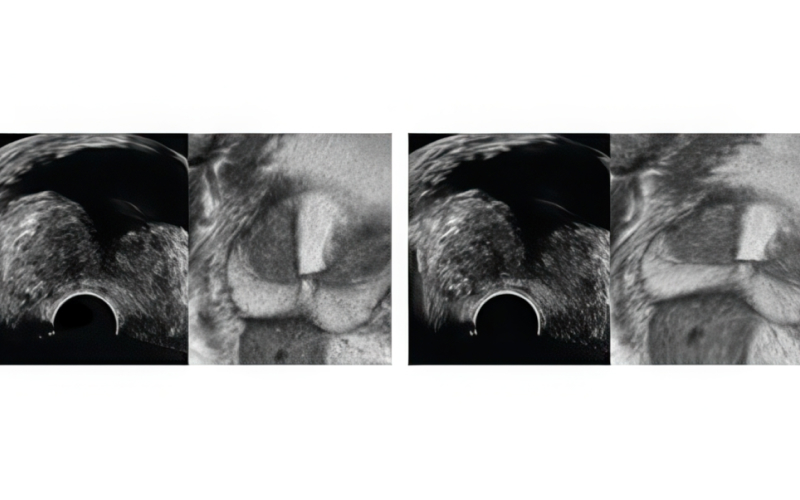

기존 검사는 병변 유무와 관계없이 12군데를 무작위로 채취해 정확도가 낮고 재검 가능성이 높았습니다. 하지만 MR 퓨전 조직검사는 병변을 직접 겨냥해 조직을 채취하므로 진단율이 크게 향상되었습니다.

· 병변을 정확히 채취 · 71.4%의 진단율 · 한 번의 검사로 끝날 확률이 높음 · 통증 ½로 감소 |

· 12군데를 무작위로 채취 · 약 25~35%의 진단율 · 재검 확률이 상대적으로 높음 · 통증 부담이 높음 |